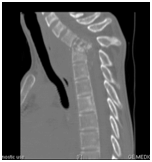

Biology showed a marked inflammatory biological syndrome: erythrocyte sedimentation rate at 130mm/H1, a C-reactive protein at 38mg/l, and a normochromic normocytic anemia at 10 g/dl of hemoglobin. Leukocytes, platelets, blood glucose, serum calcium, creatinine, ionogram, transaminases, muscle enzymes, and lipid parameters were within normal limits. X-rays of the cervical spine showed significant damage of the fifth and sixth cervical vertebrae (C5 and C6) with destruction of the vertebral bodies, narrowing of the joint space and marked thickening of the retropharyngeal space. Cervical computed tomography (CT) confirmed the diagnosis of advanced C5-C6 spondylodiscitis (Figures 1 & 2) and demonstrated a large retropharyngeal abscess exerting a mass effect on aerodigestive structures (Figure 3).

Figure 2 Sagittal cervical CT/parenchymal window: C5-C6 spondylodiscitis with retropharyngeal abscess compressing the aero-digestive structures.